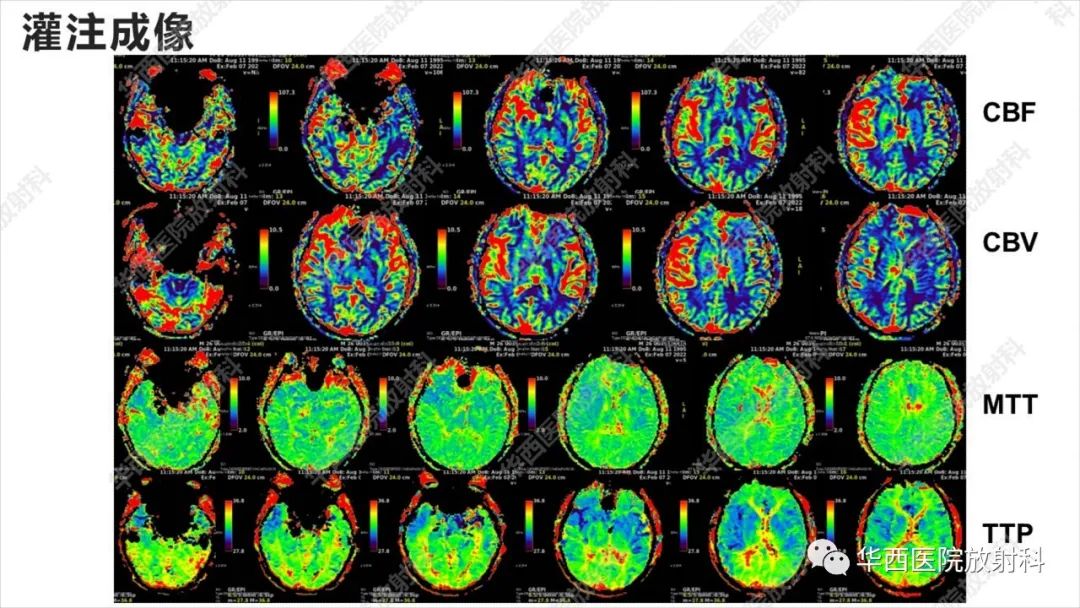

【病例】出血坏死性病毒脑膜脑炎1例CT及MR影像学表现和鉴别诊断-4